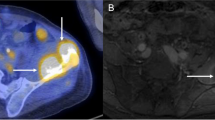

Validation of imaging findings with macroscopy

In lamb leg number 8, clear visible macroscopic lesions could be identified as focal regions of pale tissue (Fig. 7); these lesions were not visible on T1- or T2-weighted images. ADC increases of 18.1%, 21.9%, 20.7%, and 21.1% (mean 20.2%) were measured in these regions after the four exposures and were sustained 30 min after sonication. In lamb leg sample numbers 2 to 7, macroscopic lesions were also found after sonications at 120–190 W (from 1.9 to 3.0 kJ), for which ADC initially increased by 10–15%. However, difficulties in slicing the lamb legs prevented accurate identification of the lower threshold at which permanent tissue damage occurred.

Three of four thermal lesions seen after exposures to lamb leg sample 8. Macroscopic tissue changes were seen as focal regions of pale muscle tissue (white arrows) adjacent to the bone surface whose approximate outline is indicated by the white dashed lines. In these muscle tissue lesions, post-sonication ADC values were 20% higher than the pre-sonication measurements

Clear focal ex-vivo muscle tissue change was confirmed macroscopically when ADC increases of 20% were measured. The ADC increase is consistent with a breakdown of cell membranes, expected after thermal damage [26], although there was no concomitant change in T1W or T2W images. Unfortunately, contrast-enhanced imaging could not be obtained in these ex-vivo samples to confirm non-perfusion or tissue necrosis. In-vivo, contrast enhancement is the most robust way of demonstrating tissue ablation at the end of the procedure [5], but intra-procedural contrast enhanced imaging is not feasible [7].